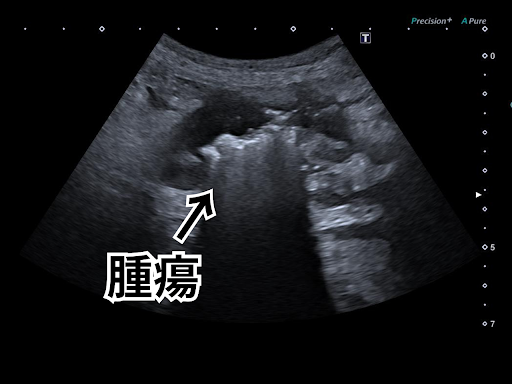

超音波検査では、腸壁の不整と腹水の貯留が確認できました。

以下が、超音波検査で確認できた腸管の不整部位の画像です。

腫瘍の周囲で腸壁の5層構造が乱れてみえます。